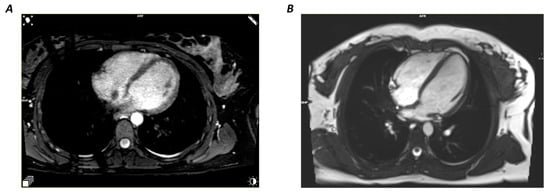

Figure 2. Comparison of the Four-Chamber View: Both 2D-cine (A) and 3D-wh (B) demonstrate high CNR and SNR, with a slight advantage in CNR for the 2D-Cine.

The study included 18 subjects with an average age of 23.6 ± 0.6 years, of which 60% were female. The required MRI sequences were successfully performed on all subjects and were free from artifacts. Table 1 demonstrates that both the 2D-cine and the 3D-wh images exhibited above-average image quality metrics. However, the 2D-cine images displayed significantly better contrast intensity (CNR) compared to the 3D-wh images, while the signal quality (SNR) remained comparable (Figure 2).